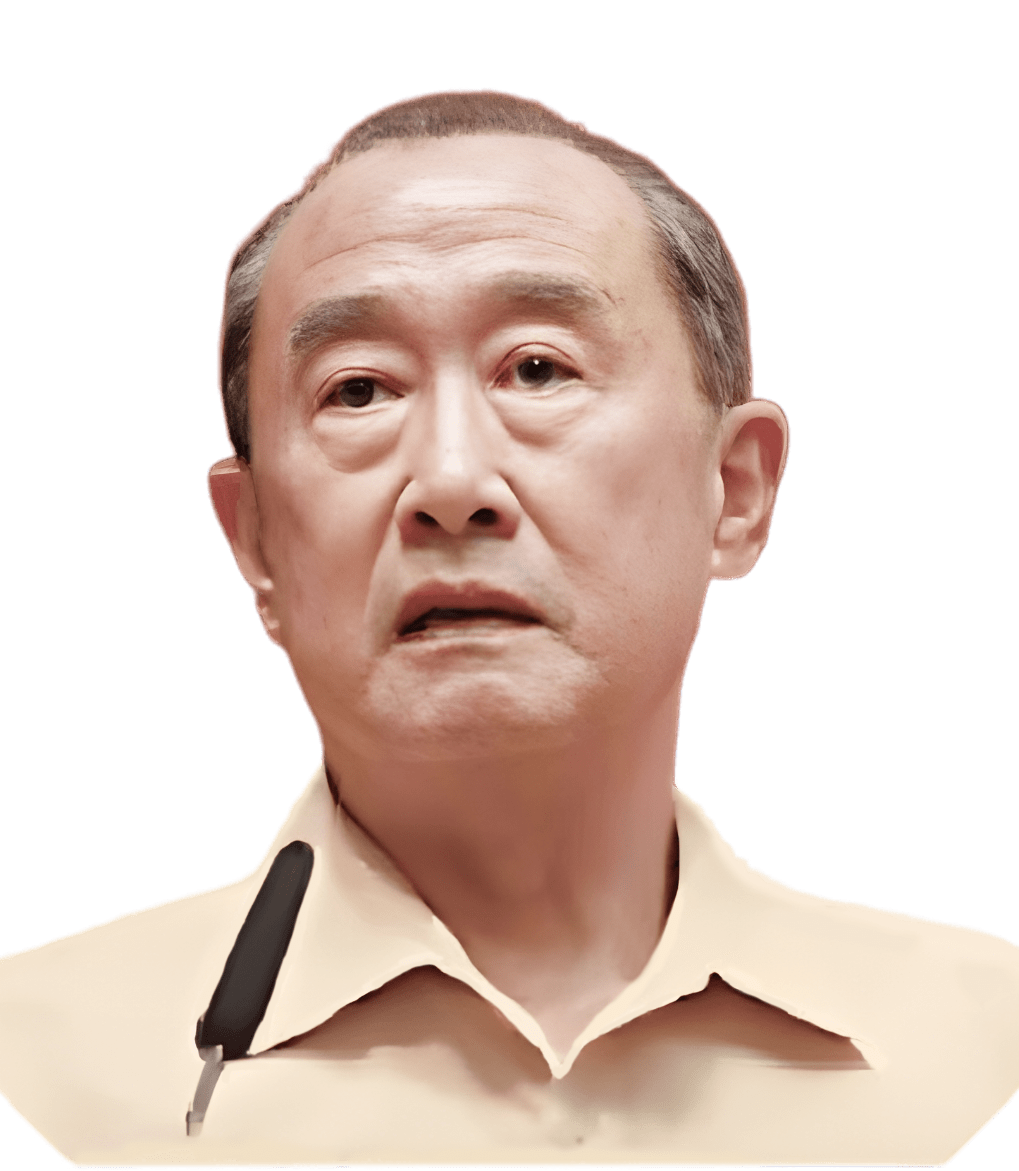

薛延

- 曾任北京积水潭医院创伤骨科研究所主任

- 中国老教授协会医药专业委员会骨质疏松与骨关节病专家组原主任

- 先后主编、参与编写19部骨质疏松的专著

- 协助组织多次全国性和国际性骨质疏松学术会议

- 曾先后获得省、部级奖励13项

- 是享受国务院特殊津贴的专家

- 1983年-1985年,赴加拿大蒙特利尔MCGILL大学医学院附属医院研修骨代谢

- 金诺三髓粉两次临床试验主研人员